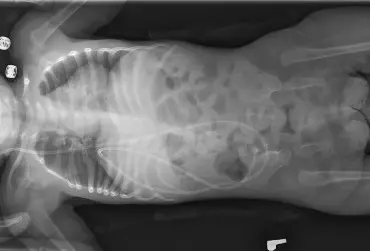

Metoda Vojty w leczeniu przepukliny oponowo-rdzeniowej

W leczeniu przepukliny oponowo-rdzeniowej bardzo istotne jest jak najszybsze rozpoczęcie terapii i pobudzenie procesów kompensacji oraz wykorzystanie możliwości adaptacji organizmu do zaburzeń czynności. Zastosowanie metody Vojty pozwala odbudować drogi nerwowe i uzyskać prawidłowy wzorzec ruchowy. Jest to metoda tania, wszechstronna i skuteczna, przede wszystkim stosowana przy czynnym udziale rodziców i w rodzinnym domu, co ma dodatkowe korzyści, jeżeli chodzi o rozwój osobowości dziecka.